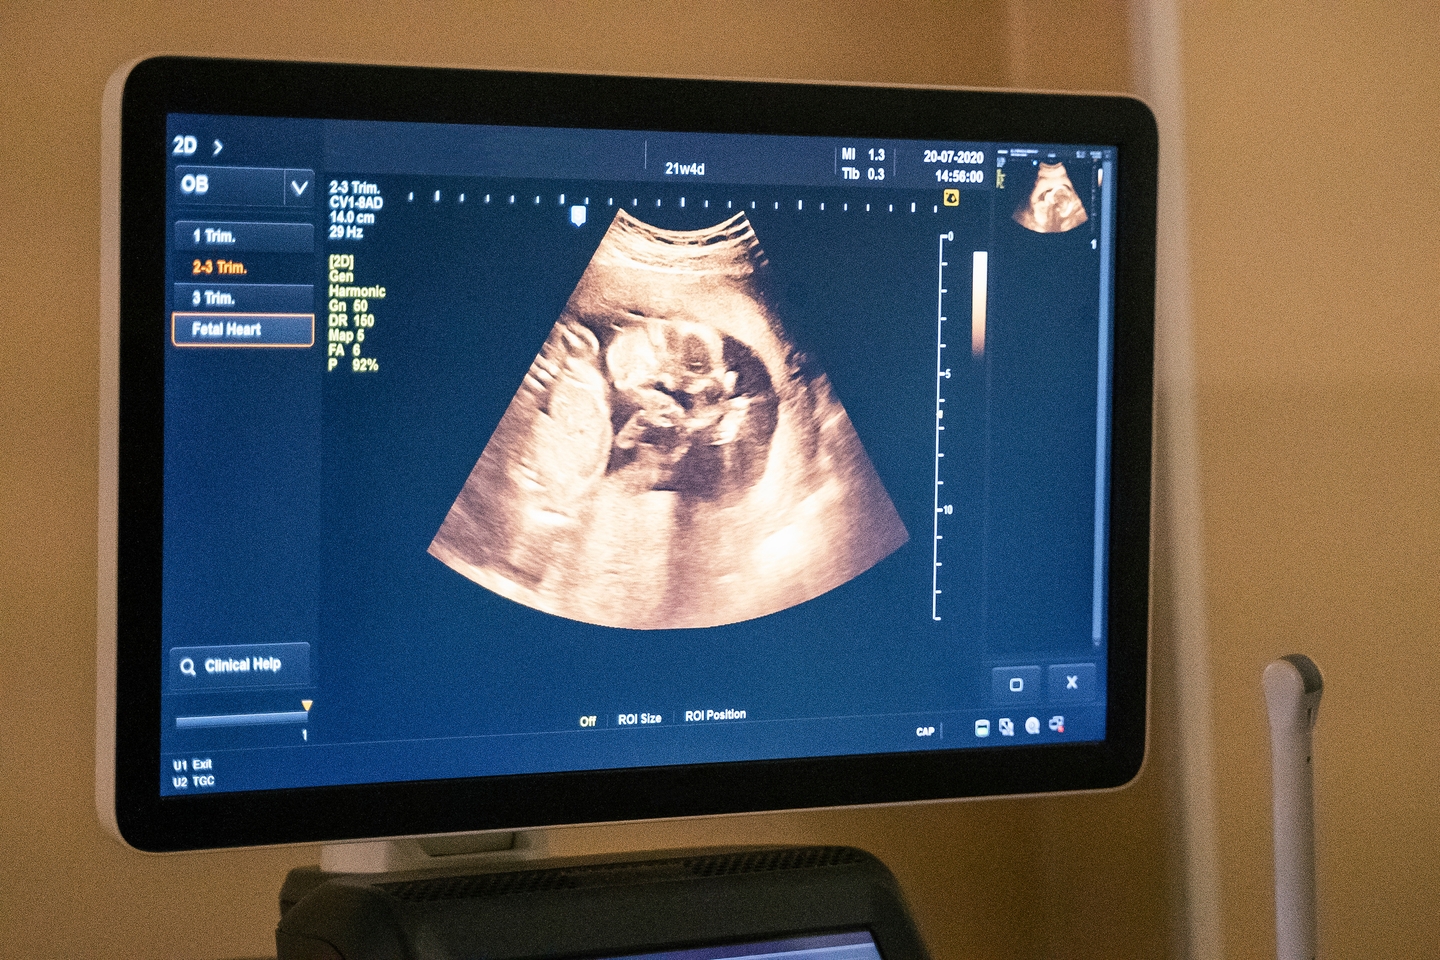

The most useful images were taken shortly before and immediately after delivery, including one that showed the baby’s head moving toward the birth canal.

This marked the first time scientists were able to clearly document how the uterine muscles contort and how the fetus rotates while making its way out of the body.